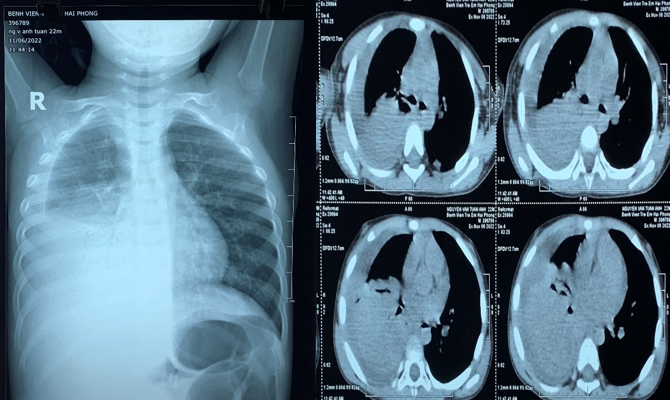

Ngày 06/11/2022, bệnh viện Trẻ em Hải

Phòng tiếp nhận trường hợp cháu Nguyễn Văn Anh T 22 tháng tuổi vào viện vì

triệu chứng ho, khó thở, sốt liên tục không đáp ứng kháng sinh đã điều trị tại

nhà 7 ngày. Trẻ được khám, làm thêm các xét nghiệm, chụp phim cắt lớp vi tính

lồng ngực. Ngay khi được mời hội chẩn, các bác sĩ khoa Ngoại Tổng hợp đã xác

định ngay đây là 1 trường hợp bệnh lí mủ màng phổi, và cần phải can thiệp sớm

bằng phẫu thuật nội soi điều trị.

Hình ảnh Xquang và chụp Cắt lớp

vi tính tràn mủ khoang màng phổi P